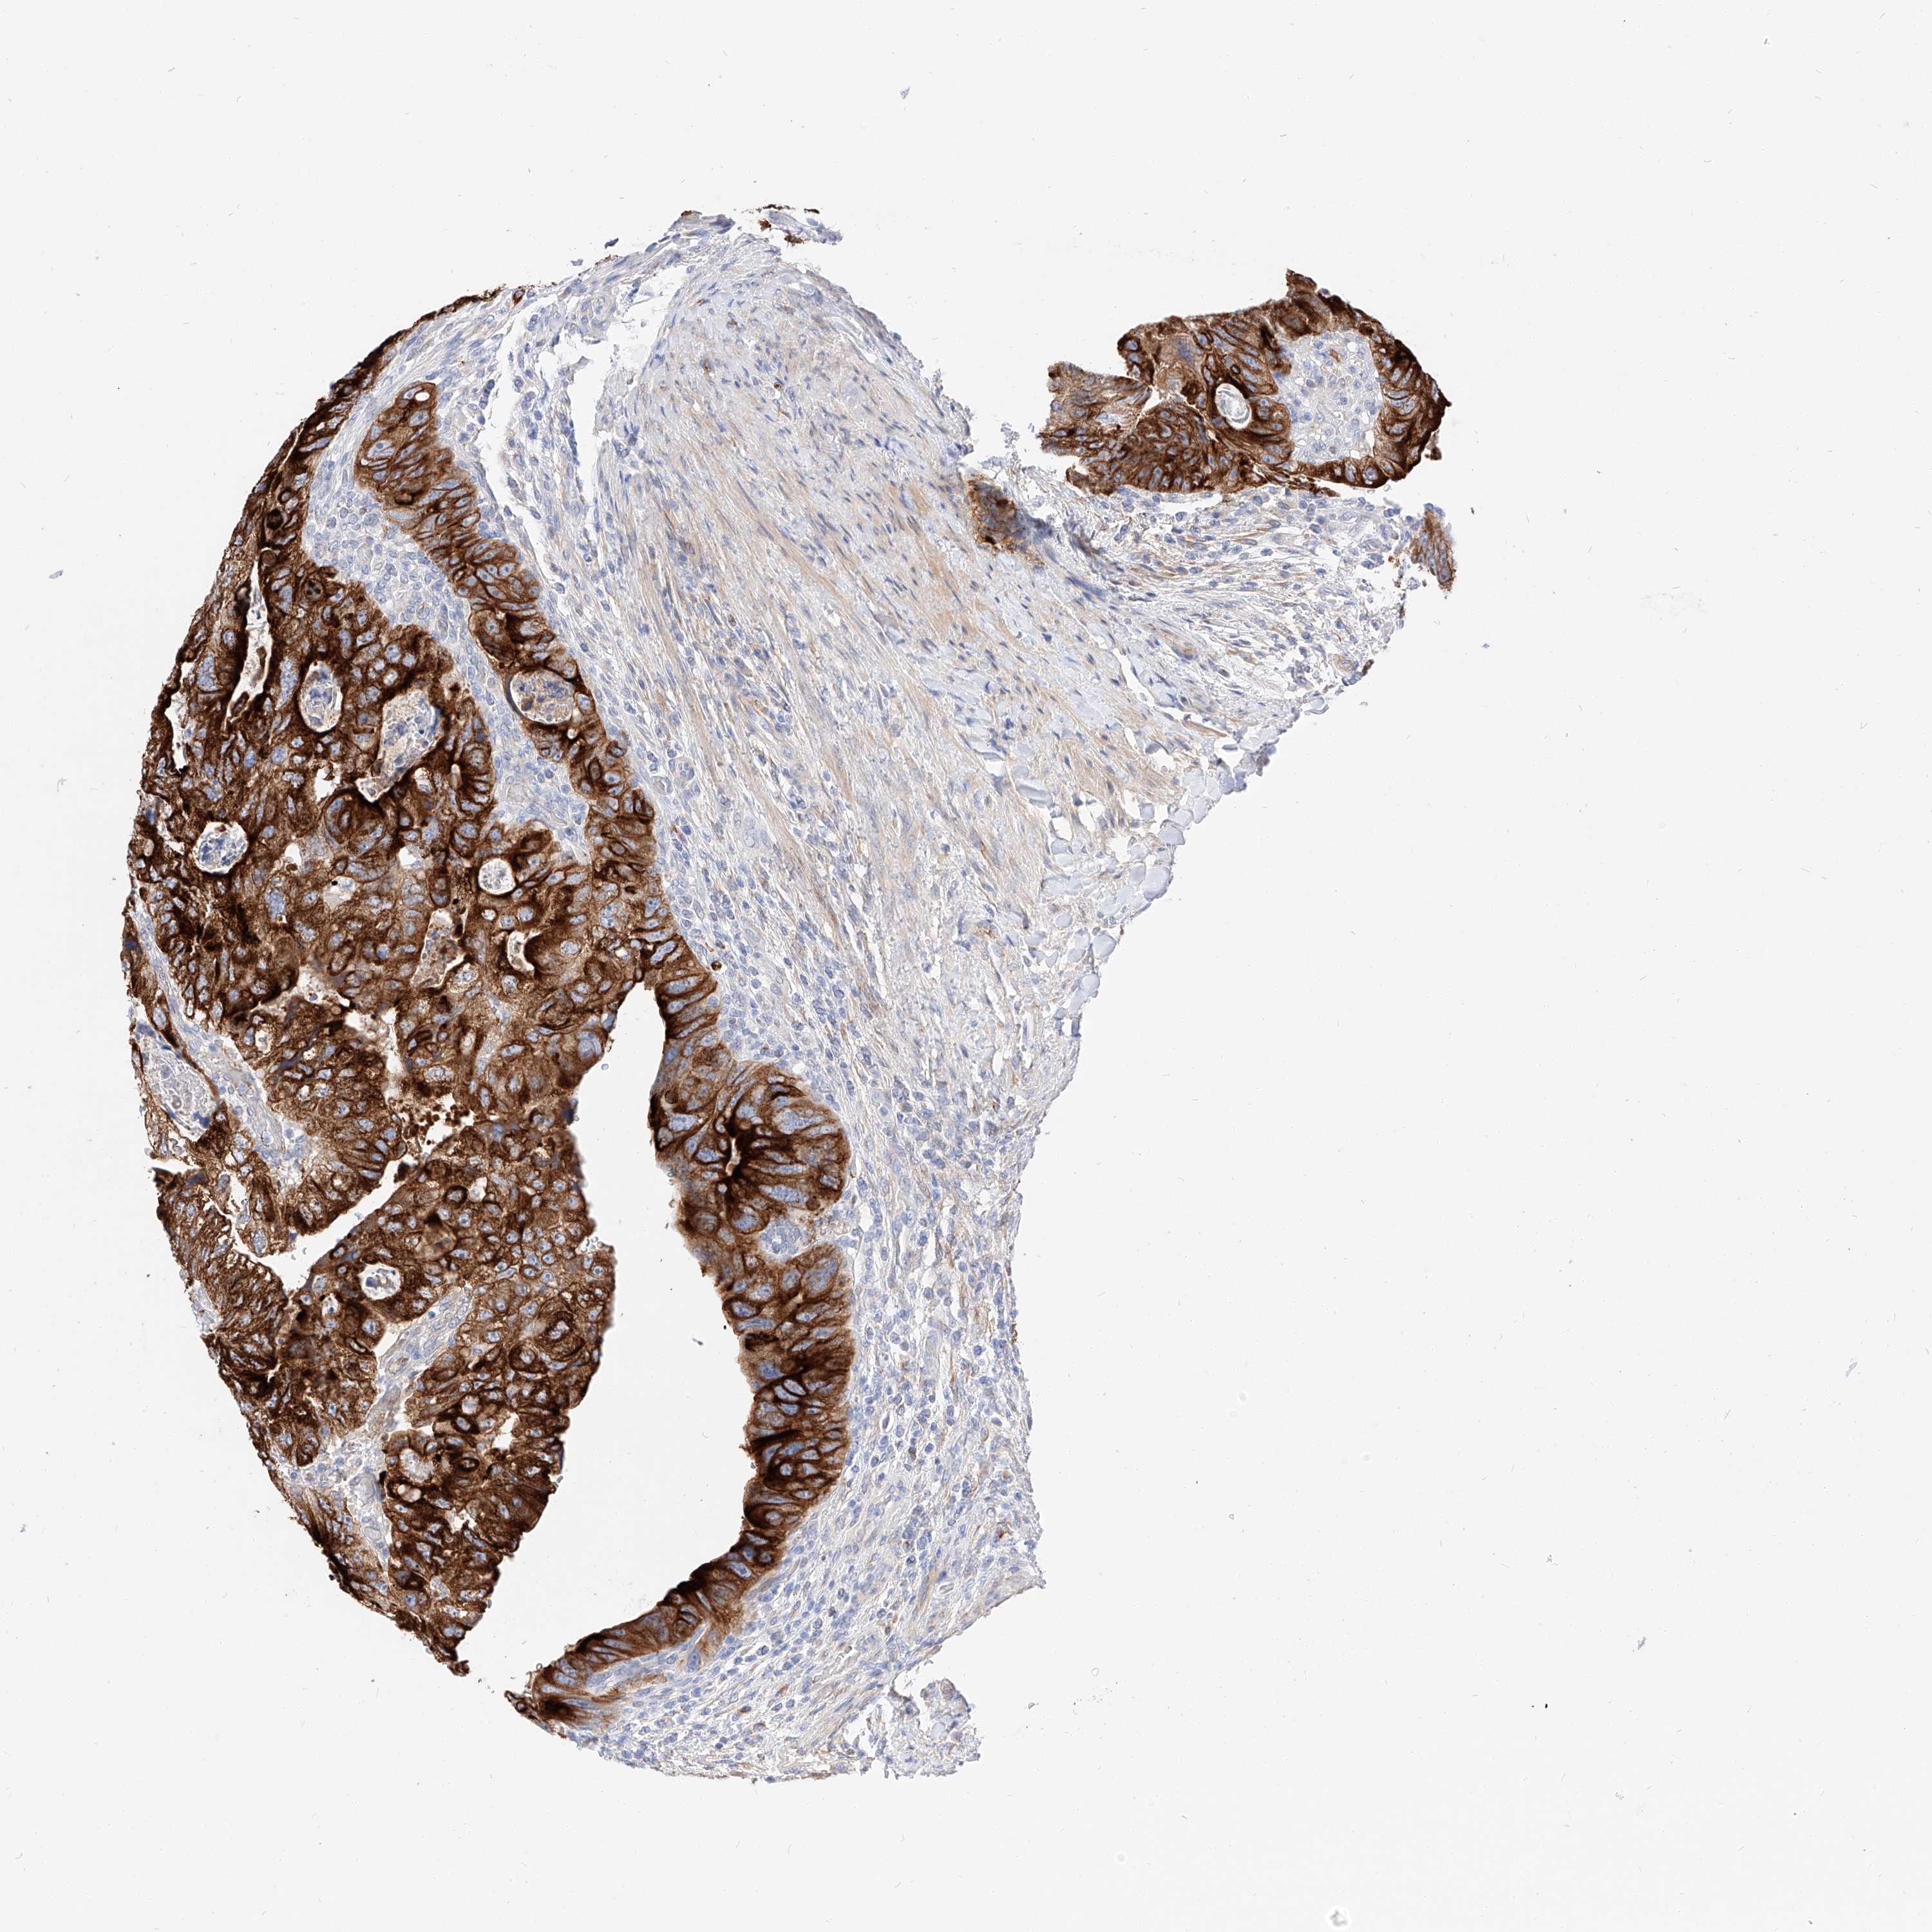

CANCER COLORECTAL CANCER Show tissue menu

Colorectal cancer

Human cancer

Colon adenocarcinoma